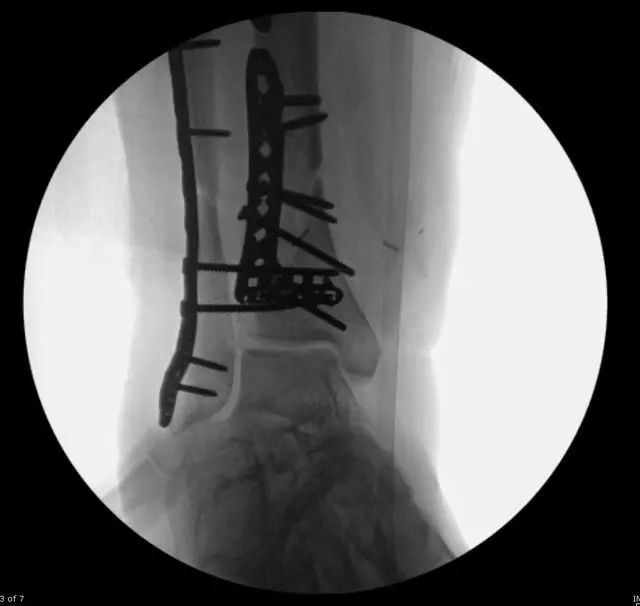

33 岁男性,车祸多发伤。左踝严重污染,几乎环形创口,胫骨远端 20 cm 缺损

游离骨块生理盐水灌洗,保持湿润,4 小时内紧急手术。术中对创口和游离骨块各用 12L 生理盐水灌洗,彻底清创。外固定支架固定,创口松散地缝合

原计划 48 小时再次灌洗,因身体情况不稳定,10 天后再次进手术室清创灌洗,方法如前;48 小时后进行了第三次灌洗,然后进行了内固定,闭合创口。

3 个月后创口无感染迹象,骨折处无压痛

6 个月后,骨折线模糊,独立行走

18 个月恢复工作